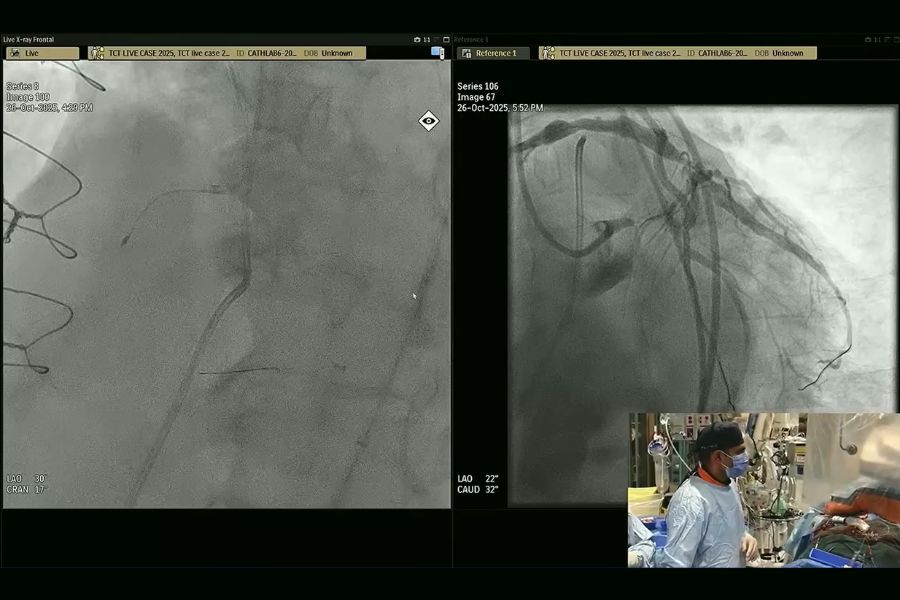

During his session at TCT, conference attendees watched as Dr. Kalra and his team performed intravascular imaging in complex PCI.

The procedure involved treating a man in his early 60s who had three of his four major heart vessels blocked.

“The patient came to the table with a confluence of three things: His heart pumping function was weak, his coronary anatomy was super complicated and he had a bunch of medical problems,” says Dr. Kalra.

At the end of the procedure, the team successfully restored blood flow to the patient’s heart vessels.